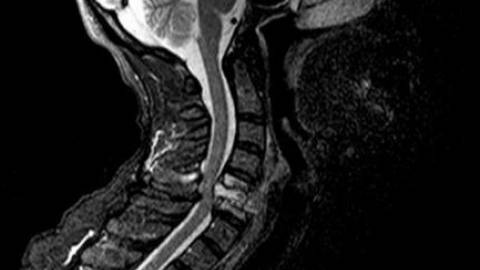

- Магнитно-резонансная томография. Наиболее популярный и информативный метод диагностирования грыжи шейного отдела позвоночника. Показателен, когда нужно получить сведения о структуре, параметрах, локализации грыжи. Если же доктора интересует состояние позвонков, лучше для этих целей прибегнуть к КТ.

- Компьютерная томография. Она дает полную картину о состоянии дисков, визуализирует локализацию небольших дефектных образований.